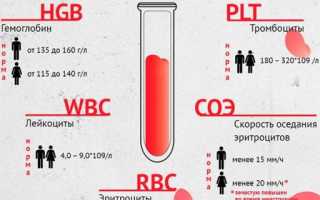

При расшифровке результатов анализа врачи обращают на такие характеристики крови:

- гемоглобин — при пиелонефрите падает;

- эритроциты — при болезни уровень снижается;

- оседание эритроцитов — показатель повышается, характерно для воспалительных процессов, протекающих в организме;

- лейкоцитоз — повышение количества лейкоцитов, сигнализирующее о борьбе организма с инфекцией;

- сдвиг лейкоцитарной формулы — сдвигается влево, диагностируется концентрация молодых нейтрофилов в крови.

Анализ крови при пиелонефрите дает и дополнительные характерные показатели. Изменение содержания протеина — показатель будет снижен (норма — 65-85 г/л).

Повышение присутствия в крови гамма-глобулинов (при норме 12-22 %) говорит об инфекционном процессе.

Воспалительные патологии, локализованные в почках, провоцируют увеличение уровня альфа-2-глобулинов в крови, количество может превышено. При повышении содержания мочевой кислоты врачи подозревают болезни органов мочевыделительной системы.

Наблюдается увеличение лейкоцитов, увеличение нормы скорости оседания эритроцитов, появление в анализе молодых лейкоцитарных форм. Эти изменения в крови имеют многие воспалительные заболевания, однако если имеется также снижение гемоглобина и падение числа эритроцитов, то специалист может заподозрить нарушение в работе почек.

Метод является ведущим, поскольку демонстрирует, какие изменения претерпевают элементы крови при развитии того или иного заболевания. В ходе исследования уделяется внимание скорости оседания эритроцитов (СОЭ), общему количеству тромбоцитов и лейкоцитов, гематокриту. О наличии воспалительного процесса свидетельствует лейкоцитурия (повышение уровня лейкоцитов), число эритроцитов и гемоглобина при этом снижено.

О предположительном наличии пиелонефрита свидетельствуют явные показатели воспалительного процесса:

- увеличение скорости оседания эритроцитов – СОЭ;

- снижение количества гемоглобина;

- уменьшение числа эритроцитов;

- повышенные показатели лейкоцитов;

- выявление молодых форм нейтрофилов.

Значения общего количества лейкоцитов являются ведущими при определении воспалительного процесса. В здоровом состоянии уровень данных компонентов анатомической жидкости составляет у ребенка от 7 до 11*109 л, у взрослых пациентов – от 5 до 9*109 л. В случае пиелонефрита количество лейкоцитов превышает верхние пределы значений. Число юных форм в норме составляет 2-5 %, при наличии заболевания – более 6%.

Гемоглобин

Задача данного компонента – переносить кислород от легких в ткани. При развитии острого воспалительного процесса его содержание в крови падает, при хронической стадии – снижается незначительно, или вообще держится в границах нижнего уровня. В норме концентрация у представительниц слабой половины составляет 120, а у мужчин – 140 г/л. При почечных нарушениях она в зависимости от формы изменяется, и отмечается на уровне 85 и 150 – у женщин, и 95 и 135 – у представителей сильного пола.